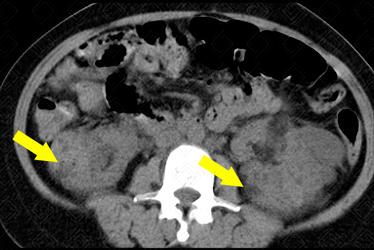

Descrição das figuras: Rins tópicos, de volume aumentado, às custas de múltiplas formações nodulares, algumas espontaneamente densas e outras com densidade de gordura, distribuídas difusamente pelo parênquima renal, bilateralmente, devendo representar cistos (setas amarelas). Destaca-se formação nodular heterogênea, com densidade predominante de gordura, no polo superior do rim direito, medindo 8,3 x 7,6 cm, compatível com angiomiolipoma (seta vermelha) Moderada esplenomegalia heterogênea, medindo 15,3 cm, às custas de pequenas formações hipodensas, devendo representar hamartomas (setas azuis). Considerar, dentre as hipóteses diagnósticas, esclerose tuberosa como a mais provável para as alterações descritas acima.

• Renais: O acometimento renal e o neurológico são as principais causas de morbimortalidade associadas a esclerose tuberosa. O mais característico são os angiomiolipomas renais (tumores renais benignos), sendo observados em cerca de 80% dos pacientes com esclerose tuberosa. Eles crescem progressivamente ao longo dos anos, com seu pico na adolescência. Estes pacientes apresentam ainda cistos renais múltiplos, hipertensão arterial, pielonefrite e doença renal progressiva. Além disso, há relatos de maior incidência de carcinoma de células renais.